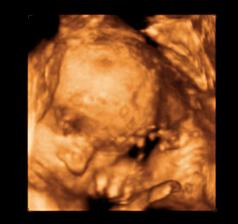

26 tt../1.4.2009/ naša paulínka je stráášne zlatá, boli sme si pozrieť na 4D utz. ..tvárila sa veľmi dôležito, až nafúkano...hehe..vôbec sa nechcela usmievať... nakoniec sa nám aj zasmiala...v brušku veľmi vyvádza, maminke dosť vytláča všetky časti telíčka, čo je niekedy aj dosť bolestivé...ale vydržíme, drobečkovi je tam určite tiež pritesno..a ešte aj stále viac a viac bude... strááášne sa na ňu tešíme🙂))